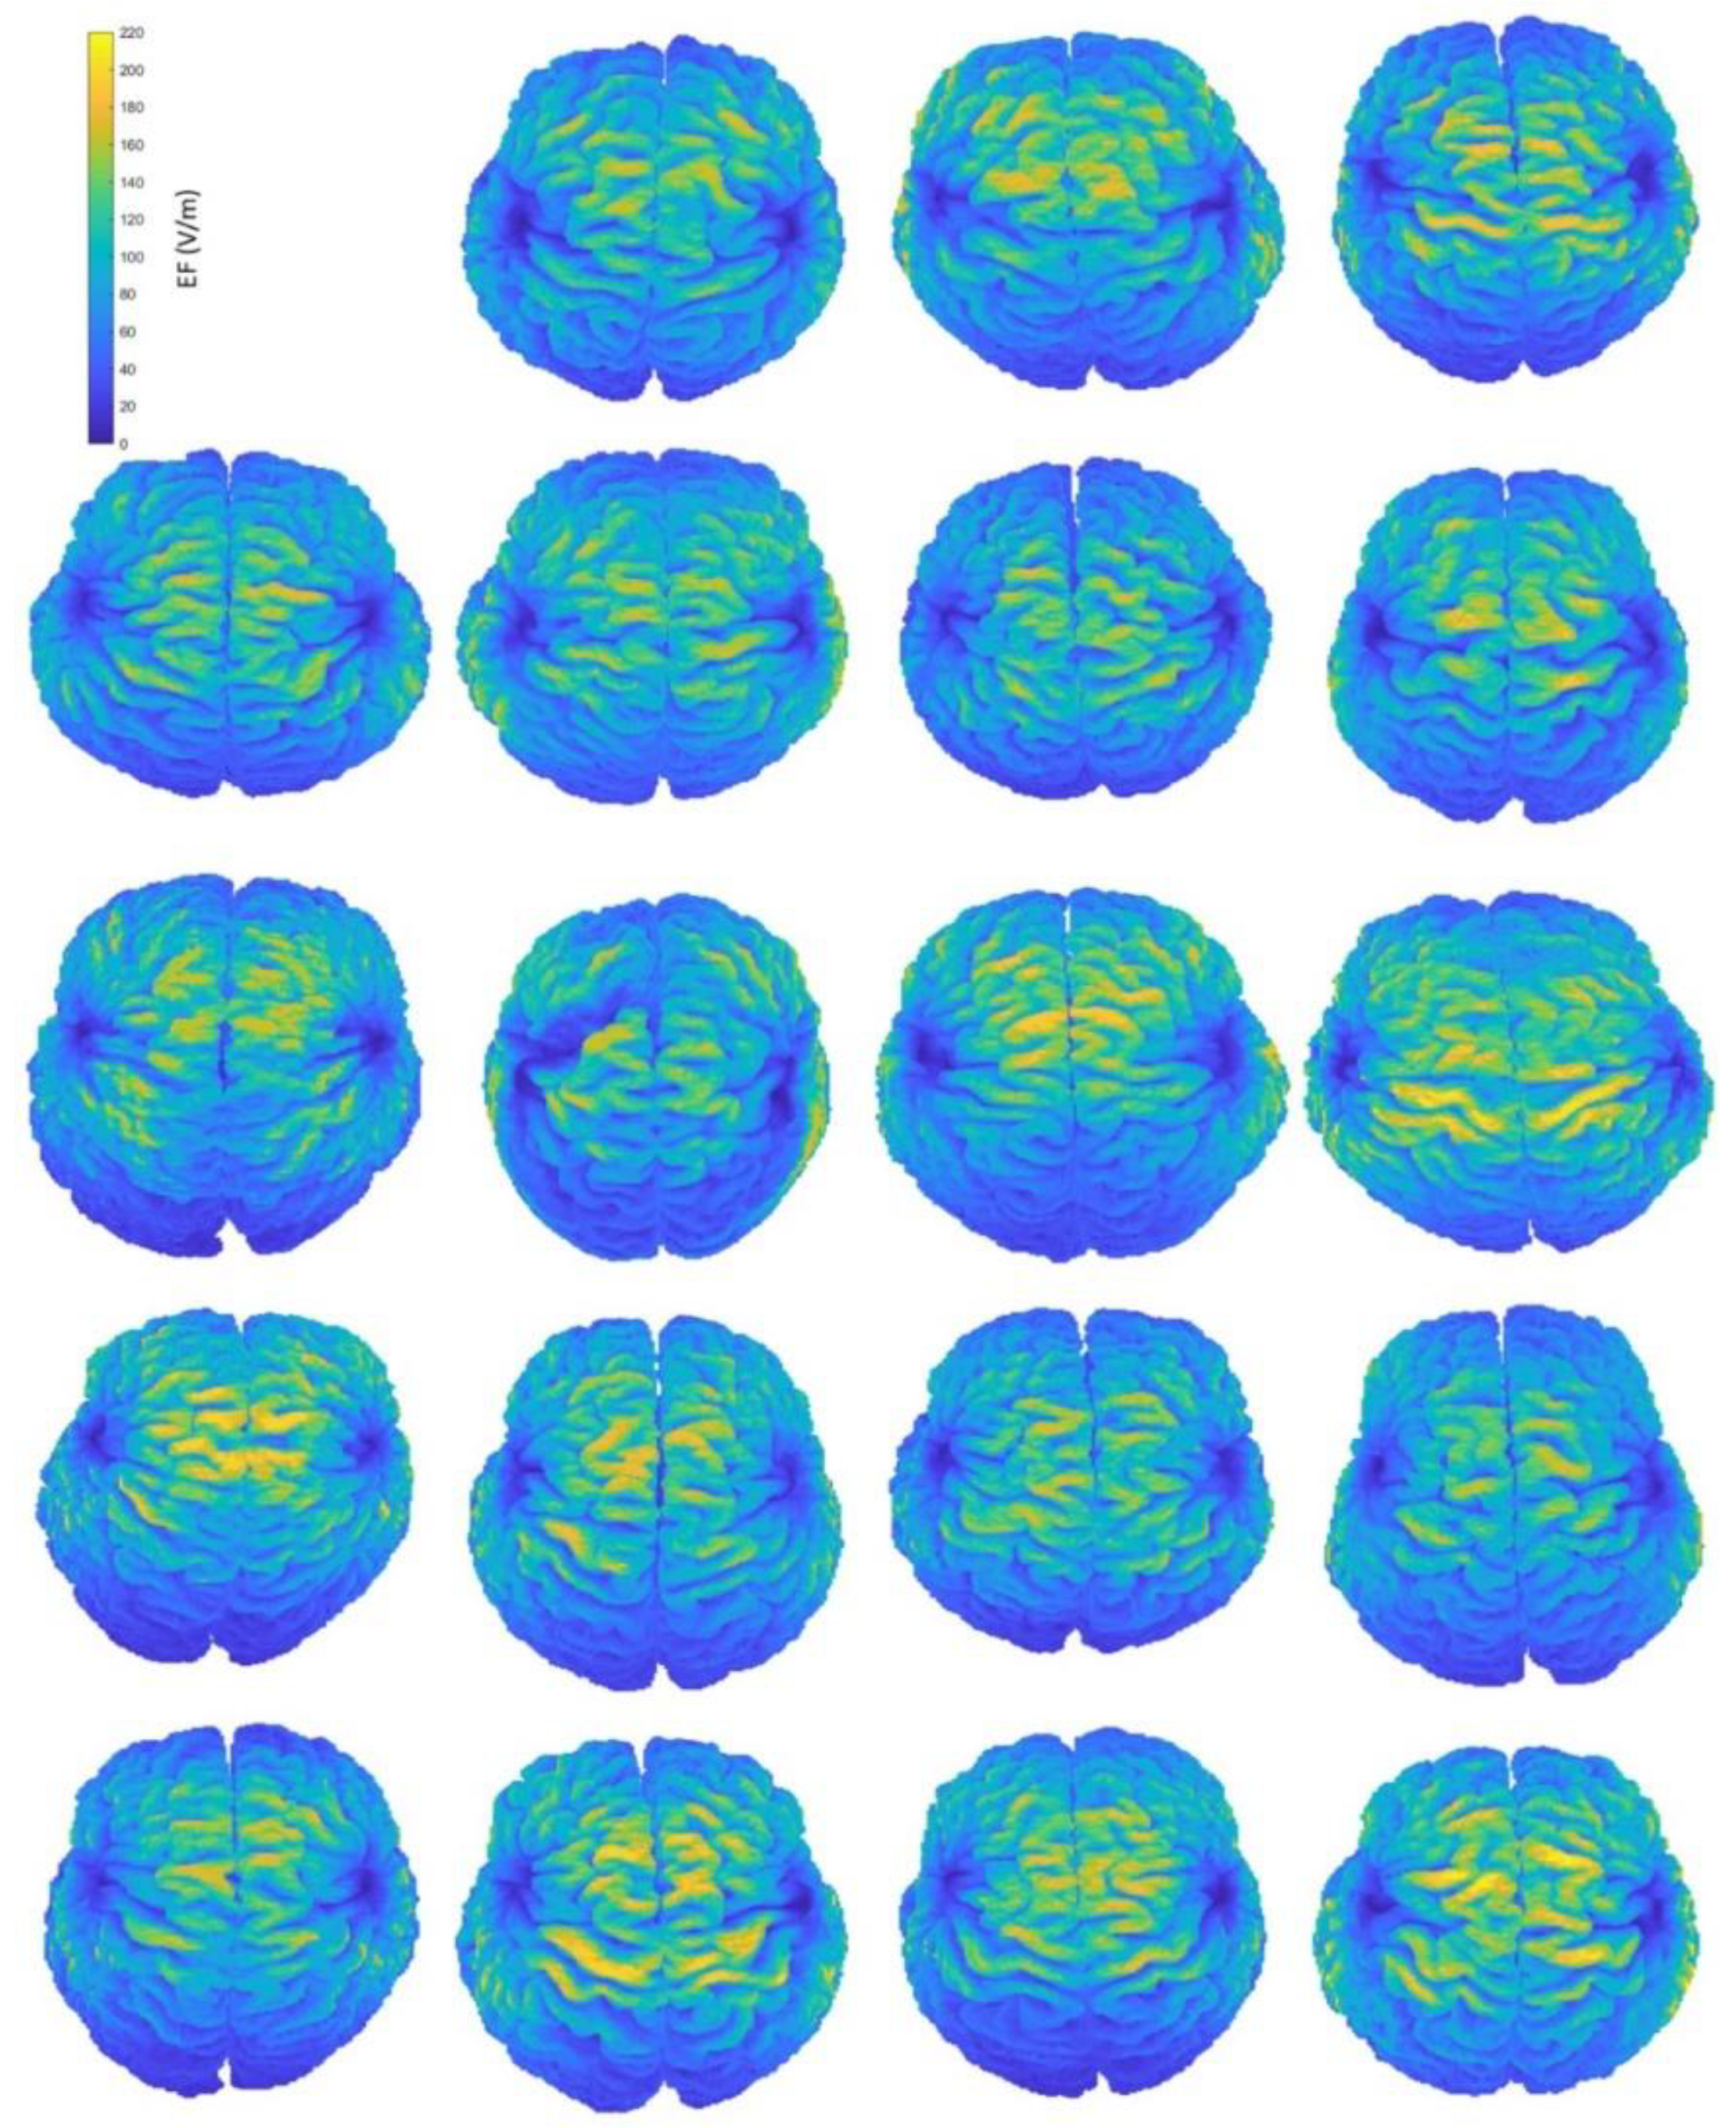

Figure A1.

Interindividual variability of the induced EF distributions visualized on subjects’ anatomical brains, containing both grey and white matter, when the coil is placed at frontal position.